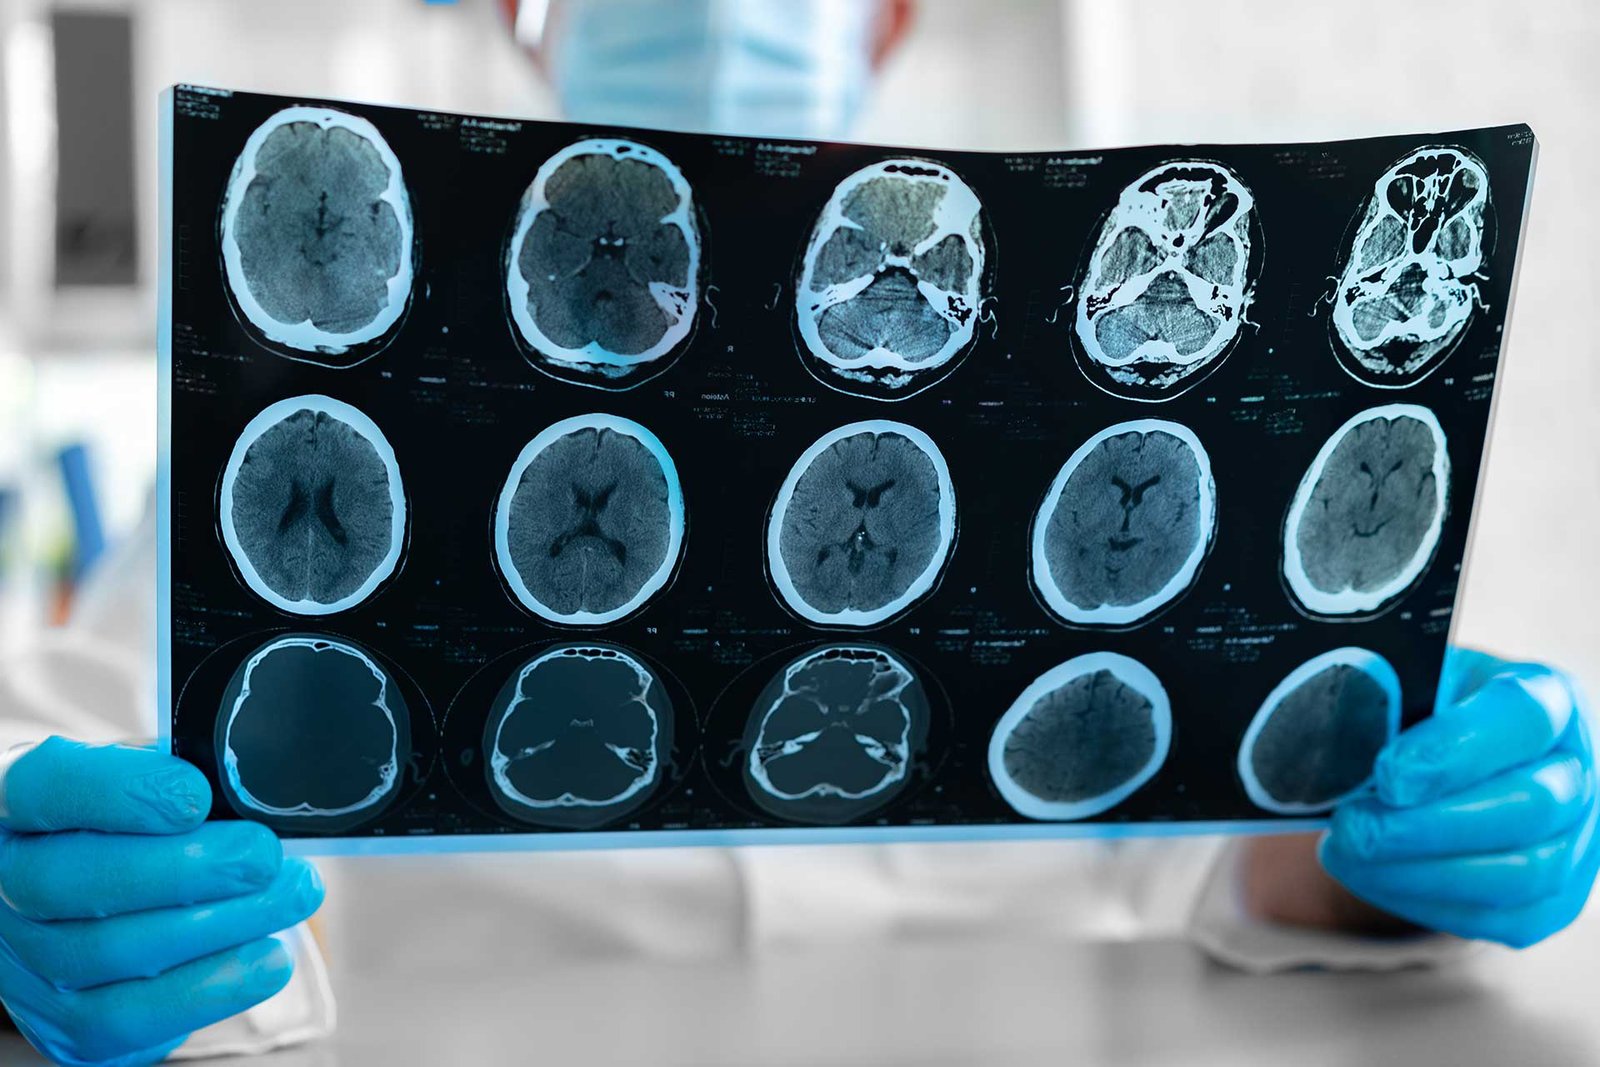

Dedicated to Neurological Excellence

With over two decades of experience in neurosurgery, I am committed to providing precise, evidence-based care tailored to each patient’s needs. My practice combines advanced surgical expertise with a compassionate approach to ensure the best possible outcomes.

Brain Surgery

Advanced procedures for tumours, trauma, and neurological disorders.

Complex Brain Tumour Removal

A delicate brain tumour was removed with minimally invasive precision, leading to full recovery and restored neurological function.